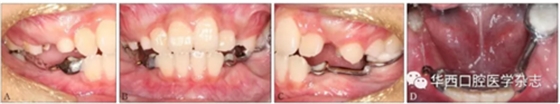

經(jīng)過綜合分析及考慮患者的意愿,制定開窗-正畸協(xié)同治療方案,術前拔除尚未萌出的45牙為牽引46牙提供間隙,通過鑄造板將36、73、32、31、42、41、83牙連接成一整體,為牽引46牙提供支抗(圖4)。

A:右側像;B:正面像;C:左側像;D:下頜面像。

圖 4 矯治器初裝口內像

46牙開窗并將舌側扣粘接于近中面。用玻璃離子將鑄造板粘接在下頜,橡皮鏈通過83牙遠中的牽引鉤和46牙上的舌側扣相連,橡皮鏈牽引時對46牙產生一個順時針旋轉的作用力。術中牽引1個月時,見46牙產生順時針旋轉(圖5、6)。治療5個月時,46牙產生明顯的順時針旋轉,基本直立(圖7),由于此時下頜雙側乳尖牙脫落,下頜鑄造板無法固位,于是拆除矯治器,觀察隨診,待后期其余牙齒萌出后行全口固定正畸矯治。

圖 5 治療1個月口內像